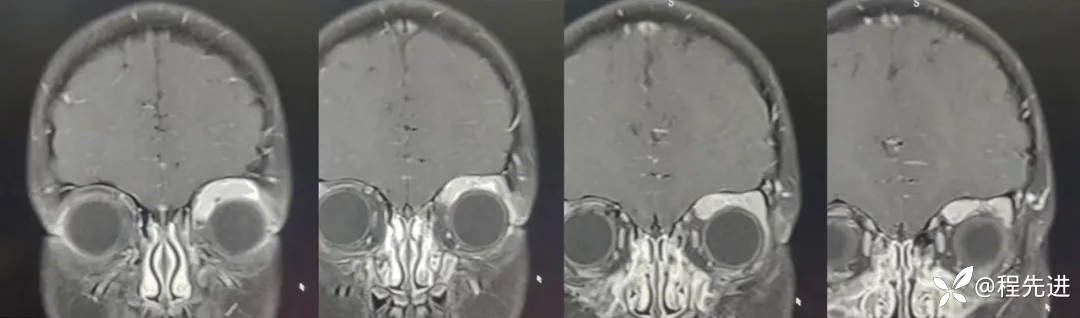

MRI平扫+增强:

T1增强: